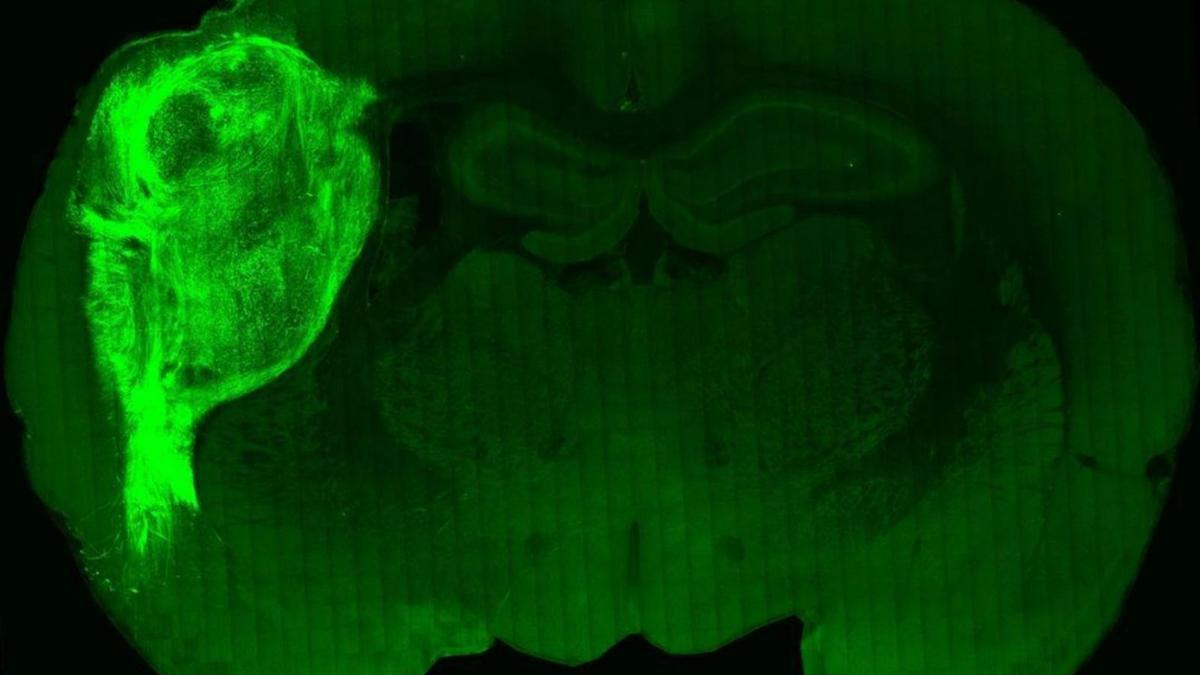

Científicos han logrado implantar en ratas recién nacidas diminutas estructuras en 3D derivadas de células madre que imitan la función de los órganos y podrían ser clave para el estudio de enfermedades. Concretamente esta novedad podría mejorar la capacidad de producir modelos realistas de enfermedades neuropsiquiátricas humanas.

No obstante, a pesar de que «el estudio tiene implicaciones importantes (…), también pone de manifiesto que la aproximación metodológica llevada a cabo presenta limitaciones importantes, dado que las diferencias entre el sistema nervioso humano y de rata pueden dar lugar a interpretaciones erróneas», advierten los investigadores en las conclusiones de su estudio.